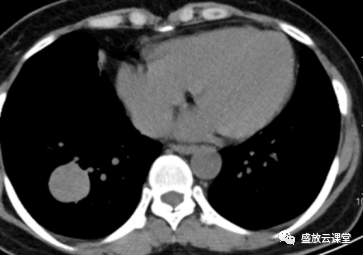

增强CT影像表现

右肺下叶基底段类圆形高密度影,大小约3.0cm×2.9cm

边缘规整,其内见点状钙化,增强扫描明显均匀强化

部位:右肺下叶、基底段

形状:类圆形

边界:边界清晰

密度:密度较均匀,其内见点状钙化

强化方式:均匀强化

影像学特点(CT):右肺下叶基底段类圆形高密度影,边缘规整,密度较均匀,其内见点状钙化,增强扫描明显均匀强化